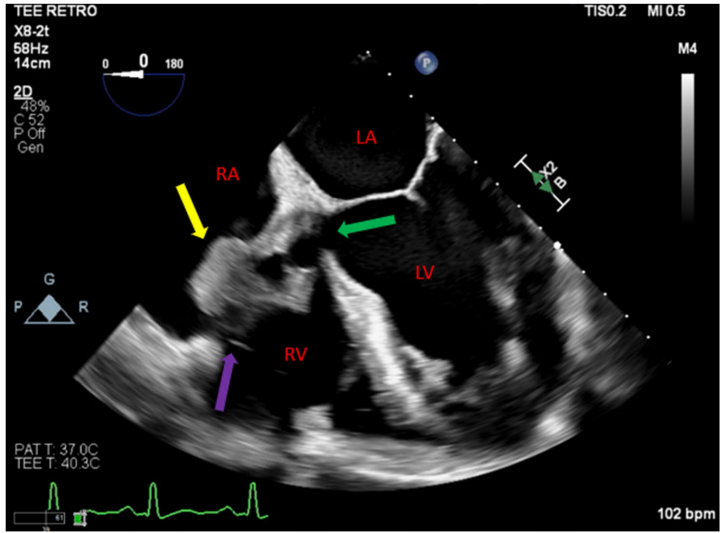

紧急TEE检查证实了室间隔完全侵蚀和生物主动脉瓣膜开裂,二维图像清晰显示右心房内大型赘生物和相关的Gerbode缺损。多普勒超声进一步显示主动脉根部感染沿瓣周扩展,室间隔膜部侵蚀入右心房,左心室流出道与右心房之间存在连续性左向右分流,并伴有重度主动脉反流。